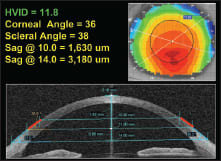

Figure 1. Corneal/scleral data, 11.0mm cornea.

As a general rule, smaller-diameter corneas exhibit less sagittal height and, conversely, larger-diameter corneas exhibit greater sagittal height (Figures 1 through 3, which profile corneas that have small, medium, and large corneal diameters). However, this is not always the case.

Topographical studies at Pacific University have shown that in normal (non-diseased) eyes, the sagittal height across a chord of 10.0mm is surprisingly consistent and contributes approximately 1,650μm to 1,750μm to the overall sagittal height. Beyond the 10.0mm chord, the eye tends to lose its curvature and forms a tangent (straight) line that extends from 10.0mm out to the limbus and sclera.